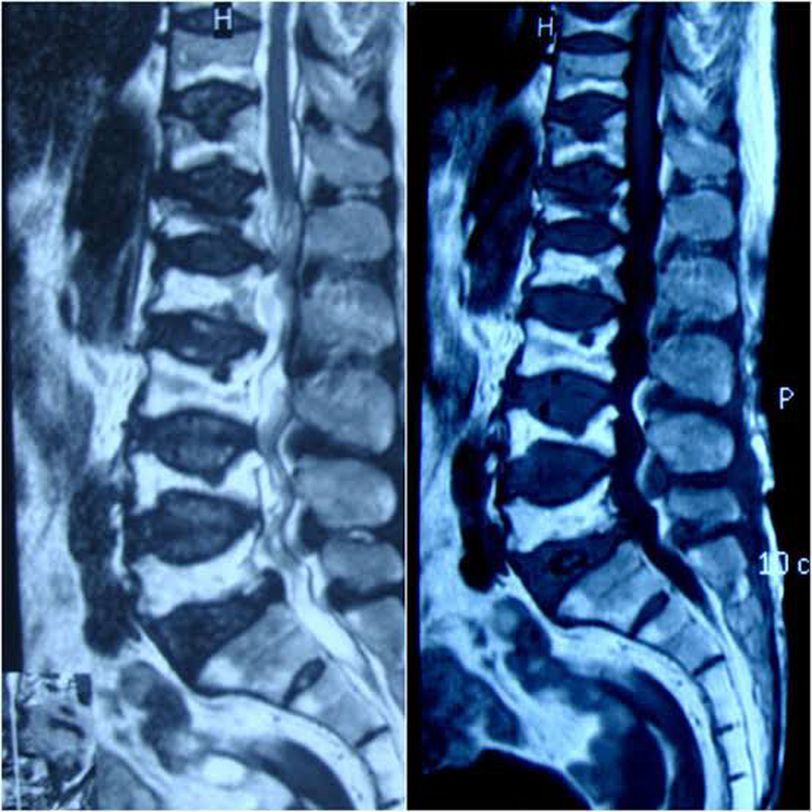

Fish Vertebrae or Codfish vertebrae is a classic radiological sign in which there is biconcave deformity of vertebral bodies. It commonly involves the Lumbar Vertebrae. This condition is usually seen in postmenopausal osteoporosis as well as disorders such as Hypoparathyroidism, Osteomalacia, Osteogenesis Imperfecta and Sickle cell anemia. Image: BMJ